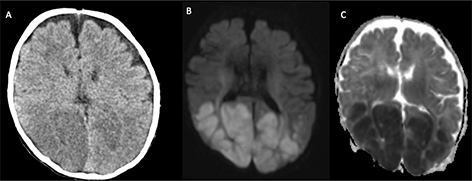

STROKE MIMICS

Clinically diagnosing stroke in neonates can be difficult due to the non-localizing and nonspecific signs of stroke, such as lateralized weakness after seizure or ataxia, are often overlooked (117). Other neurologic diagnoses can have a similar presentation, including congenital and acquired metabolic disorders, hypoglycemia, in addition to epilepsy, intracranial infection or inflammation, focal lesions, and drug toxicity (Figures 11 and 12) (118, 119).

Fig 12

Figure 12. A three-weeks-old girl with seizures and hypoglycemia. Axial CT (A) and axial DWI (B), and ADC (C) MR images show low density and loss of gray-white matter differentiation in the posterior half of the cerebral hemispheres on CT and reduced diffusion on MRI. The extent of the signal abnormality is much greater than usually seen with watershed infarction in the border zone between the MCA and PCA. Case courtesy of Dr. Tamara Feygin, Department of Radiology, Children’s Hospital of Philadelphia.